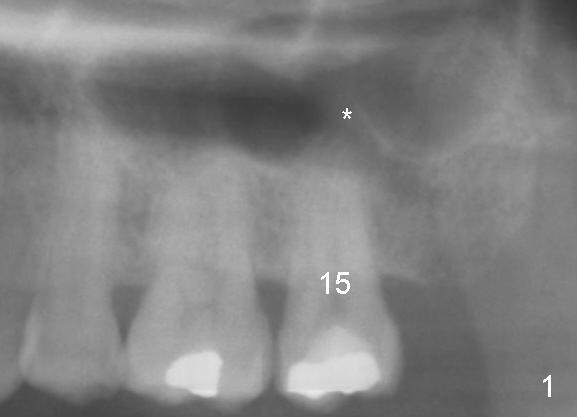

A 52-year-old black man fails to return to finish root canal therapy for the tooth #15; ultimately it is non-salvageable (Fig.1-3). The tooth has 3 basically fused roots (Fig.4 black (buccal) and red (palatal) outlines), above which is the sinus septum (*). By inserting an immediate implant into the sinus septum, primary stability should be high (Fig.5 vs. 6).